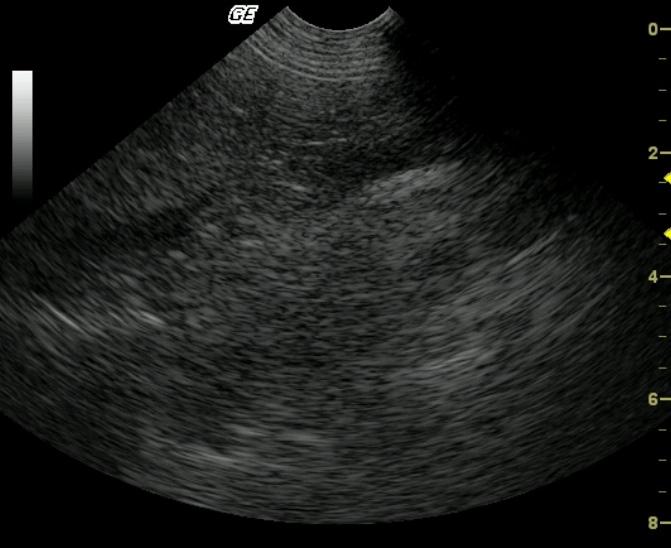

A 5-year-old FS Pit Bull Terrier dog presented for not acting right per owner, vomiting for one day, and anorexia. Temperature was normal. Initial blood chemistry revealed azotemia, low cholesterol, hyperamylasemia, and low triglycerides. CBC found thrombocytopenia. Total T4 and Pancreatic Lipase Immunoreactivity were both normal. Within a few weeks, the patient was examined again due to a decreased appetite, decreased drinking, diarrhea, several episodes of vomiting, and the possibility of toxin exposure. The dog was then admitted to the hospital for I.V. fluid therapy, blood work, urinalysis, ACTH stim., and abdominal ultrasound. Physical exam found patient weak with a doughy abdomen, depressed mentation, slight tachycardia with thready pulses, tacky mucous membranes, and five pounds of weight loss in 1.5 months. Recheck blood chemistry revealed hypoglycemia, azotemia, hyperkalemia, and hyperamylasemia. CBC was within normal limits. Urinalysis showed a normal pH and specific gravity. Hypoadrenocorticism was diagnosed on the ACTH stimulation test.